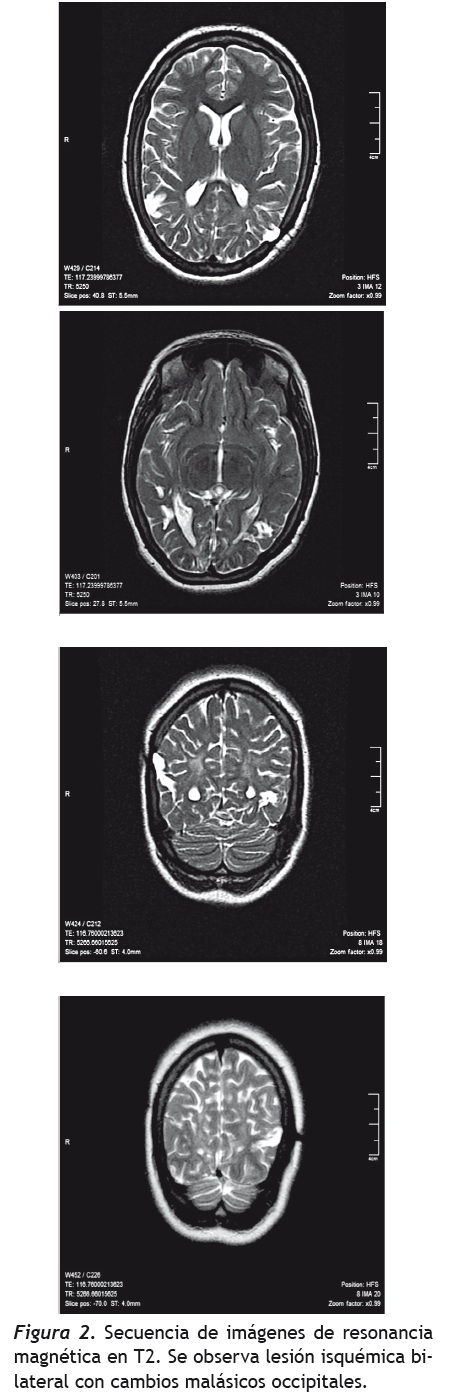

Pero también, cuando las figuras están superpuestas no puede diferenciar una de otra, lo cual corresponde con una alteración en la tercera etapa del modelo cognoscitivo propuesto por Humphreys y Riddoch (1987), la cual implica la integración de la percepción en un conjunto, con la segregación de la figura del fondo y la elaboración de una representación dependiente del punto de vista del sujeto. Riddoch y Humphreys (1987) definen la agnosia integrativa como un trastorno en el que los pacientes con lesiones occipito-temporales bilaterales son incapaces de identificar estímulos en fondos complejos, especialmente cuando se trata de formas superpuestas o entrelazadas. La agnosia integrativa también es asociada con déficits en la codificación del todo a partir de las partes presentes, a pesar de que estos pacientes pueden responder a algunos aspectos indiferenciados de las formas holísticas. Los fallos en el reconocimiento ocurren cuando la descripción holística es insuficiente para la identificación del objeto, siendo el reconocimiento de objetos enteros perturbado por el fracaso en el agrupamiento de las partes (Riddoch & Humphreys, 2003, 2004; Oliveros, 2007). En nuestro caso, en cuanto a las áreas cerebrales afectadas, la paciente presenta un foco epiléptico occipital izquierdo, sin embargo, en las imágenes cerebrales se encuentran alteraciones occipitales bilaterales. Además, se debe tener en cuenta que la paciente presenta una frecuencia elevada de crisis, posiblemente con diferentes vectores de propagación que no solamente deben producir alteraciones ipsilaterales, sino que también deben afectar el hemisferio contralateral, lo cual corresponde a lo planteado por Humphreys & Riddoch respecto a las áreas cerebrales involucradas (1987). Pero por otra parte, en sus desempeños neuropsicológicos, se encuentran estas alteraciones cognitivas que se corroboran con los hallazgos en pruebas como las de figuras superpuestas, ya que no puede integrar la totalidad de los estímulos, por lo que se centra en un detalle específico siendo incapaz de integrarlo con las otras partes que lo conforman y llevándola a generalizaciones erróneas (ej.: al mostrarle una piña se centra únicamente en la parte superior de la misma, asociándola con una palmera, a partir de lo cual empieza a tener intrusiones con elementos del mar, tratando de generalizar su respuesta).